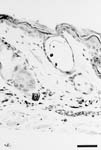

Caption: Balding Dsg3tm1Stan/Dsg3tm1Stan mice exhibit slightly cystic telogen hair follicles that lack a hair shaft (details)

Represented Alleles:

Dsg3tm1Stan, desmoglein 3; targeted mutation 1, John R Stanley

Copyright: This image is from Koch PJ, J Cell Biol 1997 Jun 2;137(5):1091-102, and is displayed under the terms of the Creative Commons Attribution-Noncommercial-Share Alike 3.0 Unported License. J:40804